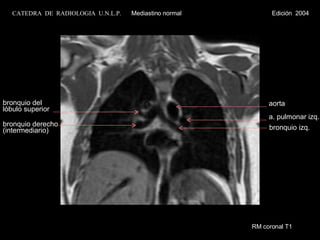

bronquio izq. a. pulmonar izq. bronquio del lóbulo superior aorta bronquio derecho (intermediario) RM coronal T1 CATEDRA  DE  RADIOLOGIA  U.N.L.P.   Mediastino normal  Edición  2004

bronquio izq. a.pulmonar izq. bronquio del lóbulo superior aorta bronquio derecho (intermediario) RM coronal T1 CATEDRA DE RADIOLOGIA U.N.L.P. Mediastino normal Edición 2004